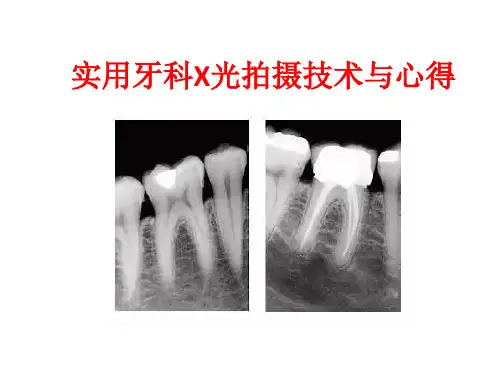

牙科X光及拍摄方法牙科X光技术是现代牙科诊疗的重要工具之一,它能够提供牙齿、牙根和周围组织的高清影像,有助于牙医准确诊断和制定治疗方案。

一、牙科X光的基本原理牙科X光技术主要利用X射线穿透人体组织的特性,通过不同密度的组织对X射线的不同吸收程度来形成影像。

牙齿由于其钙质成分较高,对X射线的吸收能力较强,因此在X光片上呈现出明亮的影像。

而周围组织如牙龈、颌骨等密度较低,对X射线的吸收较弱,在X光片上则呈现出较暗的影像。

二、常见的牙科X光拍摄方法1. 牙片X光片(Periapical X-ray)牙片X光片是最常见的牙科X光拍摄方式,它可以显示单个牙齿的形态、根尖周围组织以及牙槽骨的情况。

拍摄时,患者需要将X光片置于口腔内与要拍摄的牙齿紧密贴合,然后由牙科医生使用X射线机进行照射。